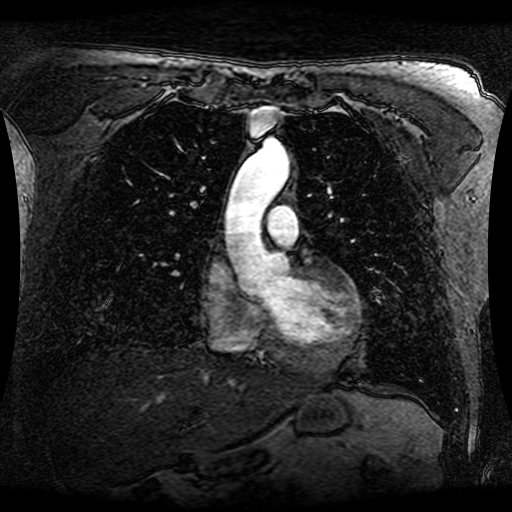

These magnetic resonance angiography (MRA) images show coronal slices acquired from consecutive anteroposterior positions within the torso. The study was performed on a 1.5T General Electric (GE) Signa imaging system with gadolinium-contrast-enhancement for visualization of the cardiopulmonary vasculature. The pulse sequence used was a 3D time-of-flight fast spoiled gradient recalled acquisition in steady state (FSPGR, TR=6.3, TE=1.4, NEX=1, FOV = 40cm, slice thickness = 1.2mm).

This sample image contains 76 frames. It is available in DICOM format (E1154S7I.dcm), as an animated GIF (E1154S7I.gif), as .ogg, .mp4, .webm, and .swf animations (one of which is shown above), or as individual PNG-format frames (see below).